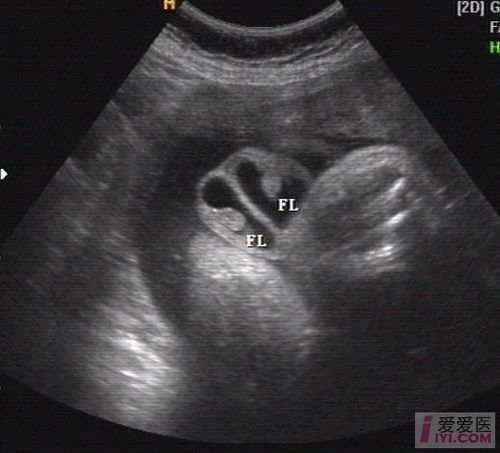

二维超声:胎儿双侧阴囊内可见睾丸回声(图 1).

男婴胎儿阴囊b超图

胎儿阴囊b超图片